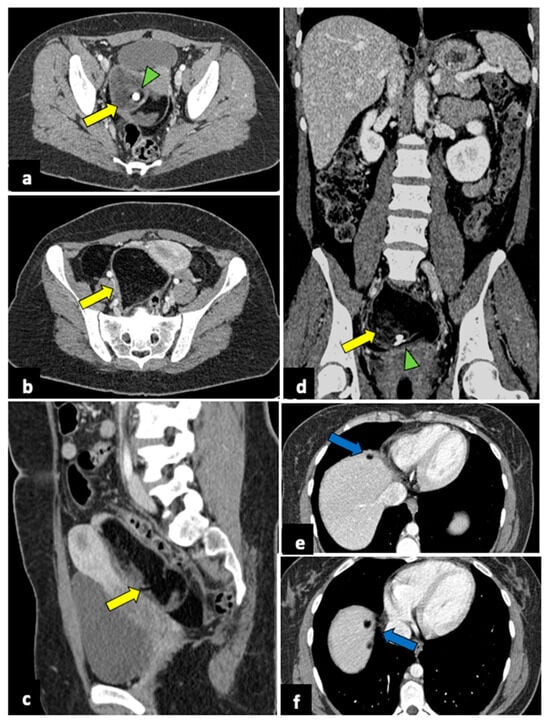

Pelvic malignancies, most commonly ovarian, cervical, and endometrial uterine cancers, can induce pain of different intensities and durations. Gynaecological cancer may present with sudden onset in cases of advanced stages, with the invasion of adjacent structures that lead to several complications, such as intestinal perforation, thrombosis, and intestinal or ureteral obstruction (Figure 10) [71,72,73].

Figure 10.

Advanced uterine cervical cancer in a 58-year-old subject attending the emergency department for abdominal pain and haematuria. CT axial (a), sagittal (b), and coronal (c) non-contrast images reveal the presence of a pelvic mass (blue arrows) and ureter causing ureteral obstruction (yellow arrows). The patient further underwent an MRI examination (d–f), which demonstrated a cervical tumour (blue arrows) invading the parametrium and ureters bilaterally (yellow arrows), the vagina, and the bladder. The uterine cavity was also obstructed and dilatated (red arrows).